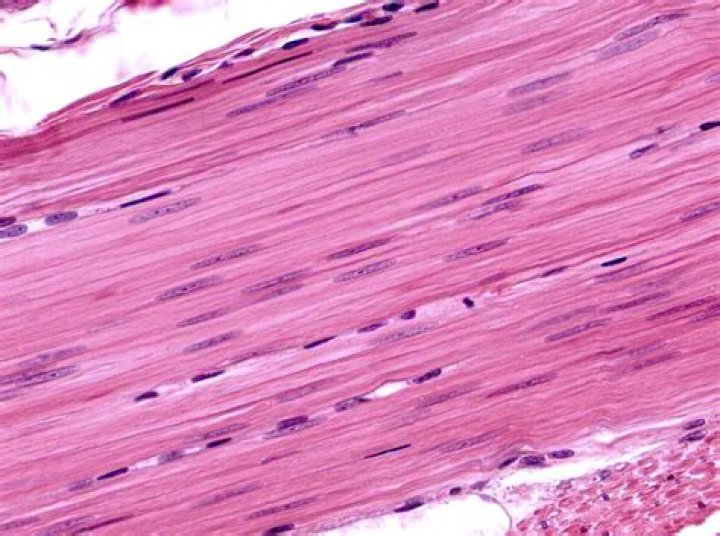

What are smooth muscle cells?

Smooth muscle cells are spindle-shaped and have single elongated nuclei. ... Smooth muscle cells contain thin (actin) and thick (myosin) contractile filaments as well as cytoskeletal filaments. The thin filaments are the most conspicuous feature of smooth muscle cells.

Which muscles are known as the smooth muscles?

smooth muscle, also called involuntary muscle, muscle that shows no cross stripes under microscopic magnification. It consists of narrow spindle-shaped cells with a single, centrally located nucleus. Smooth muscle tissue, unlike striated muscle, contracts slowly and automatically.